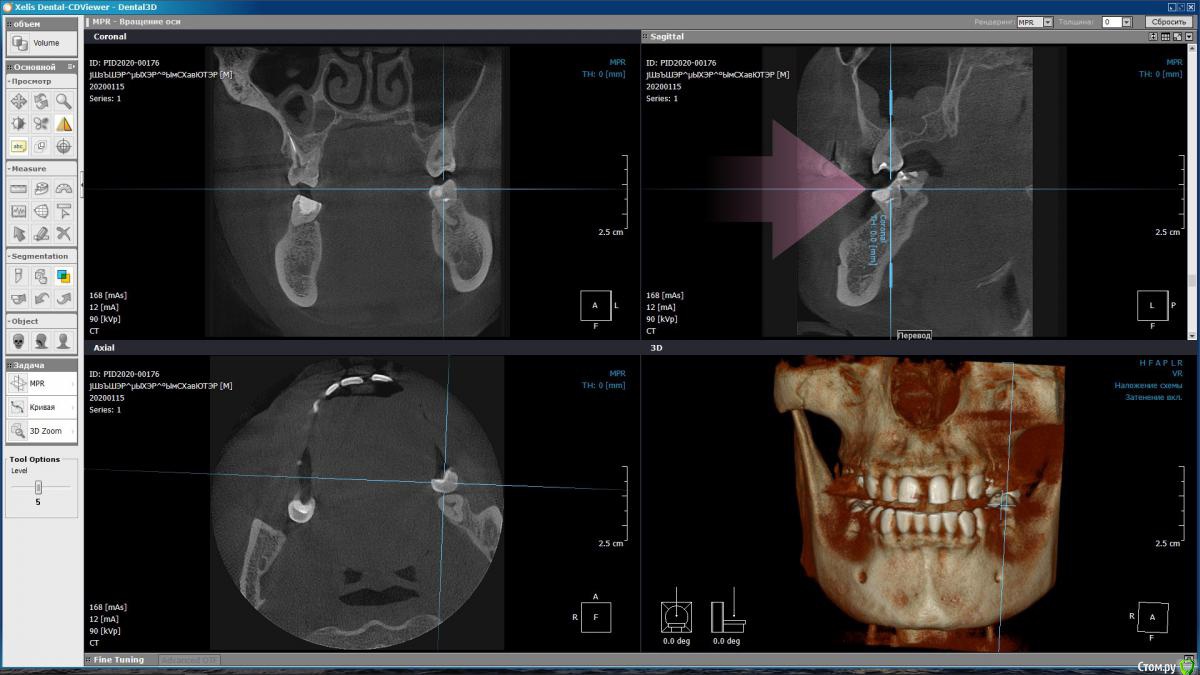

m-e-a Опубликовано 19 января, 2020 Автор Поделиться Опубликовано 19 января, 2020 (изменено) Сделала срезы как смогла, не умею я смотреть КТ Изменено 19 января, 2020 пользователем m-e-a Ссылка на комментарий

red_butler Опубликовано 19 января, 2020 Поделиться Опубликовано 19 января, 2020 На представленных срезах, показаний к удалению не увидел. Нужно смотреть очно и «крутить» Кт Ссылка на комментарий